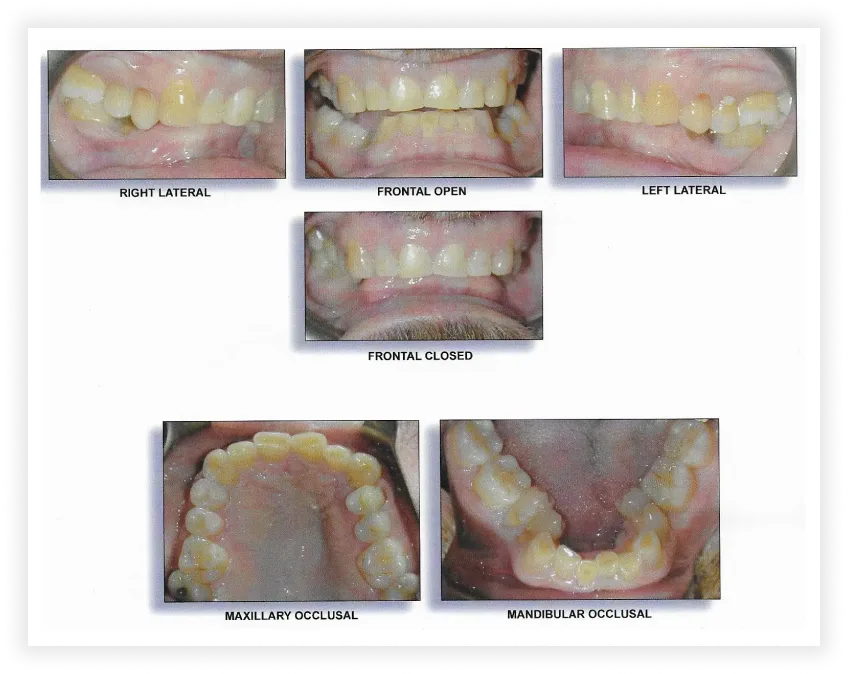

Case #2

Initial Photos

Final Photos